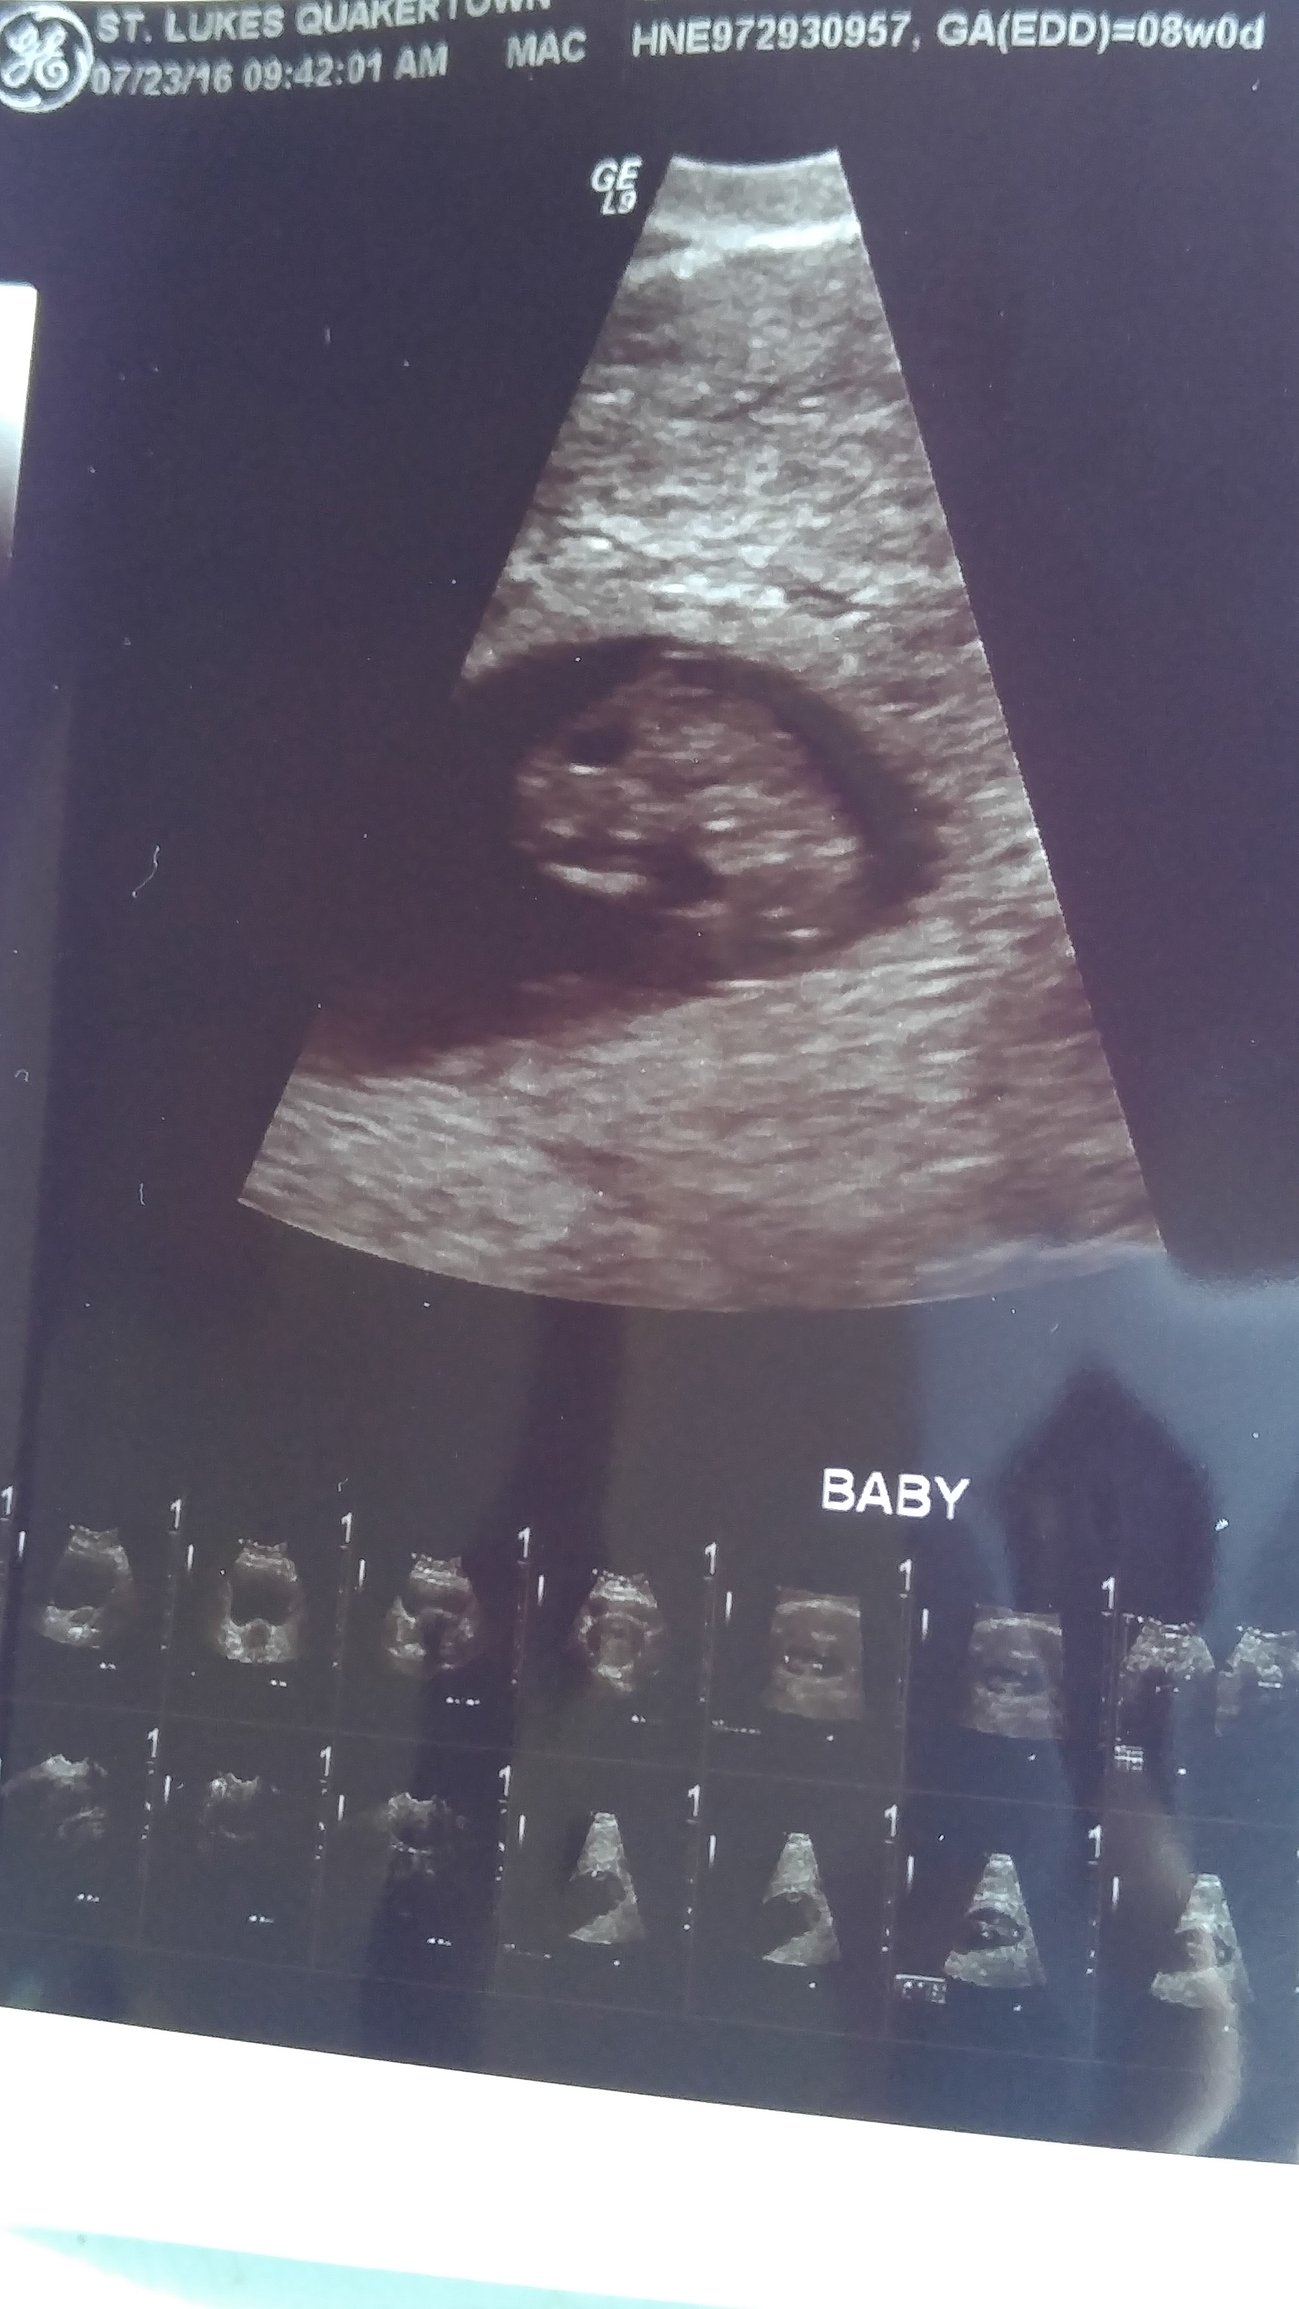

This was the blob as of today, 8 weeks. This was my first regular ultrasound instead of vaginal. I actually think I prefer vaginal because it is much clearer. But either way so happy to see it again. Heart rate was 169.